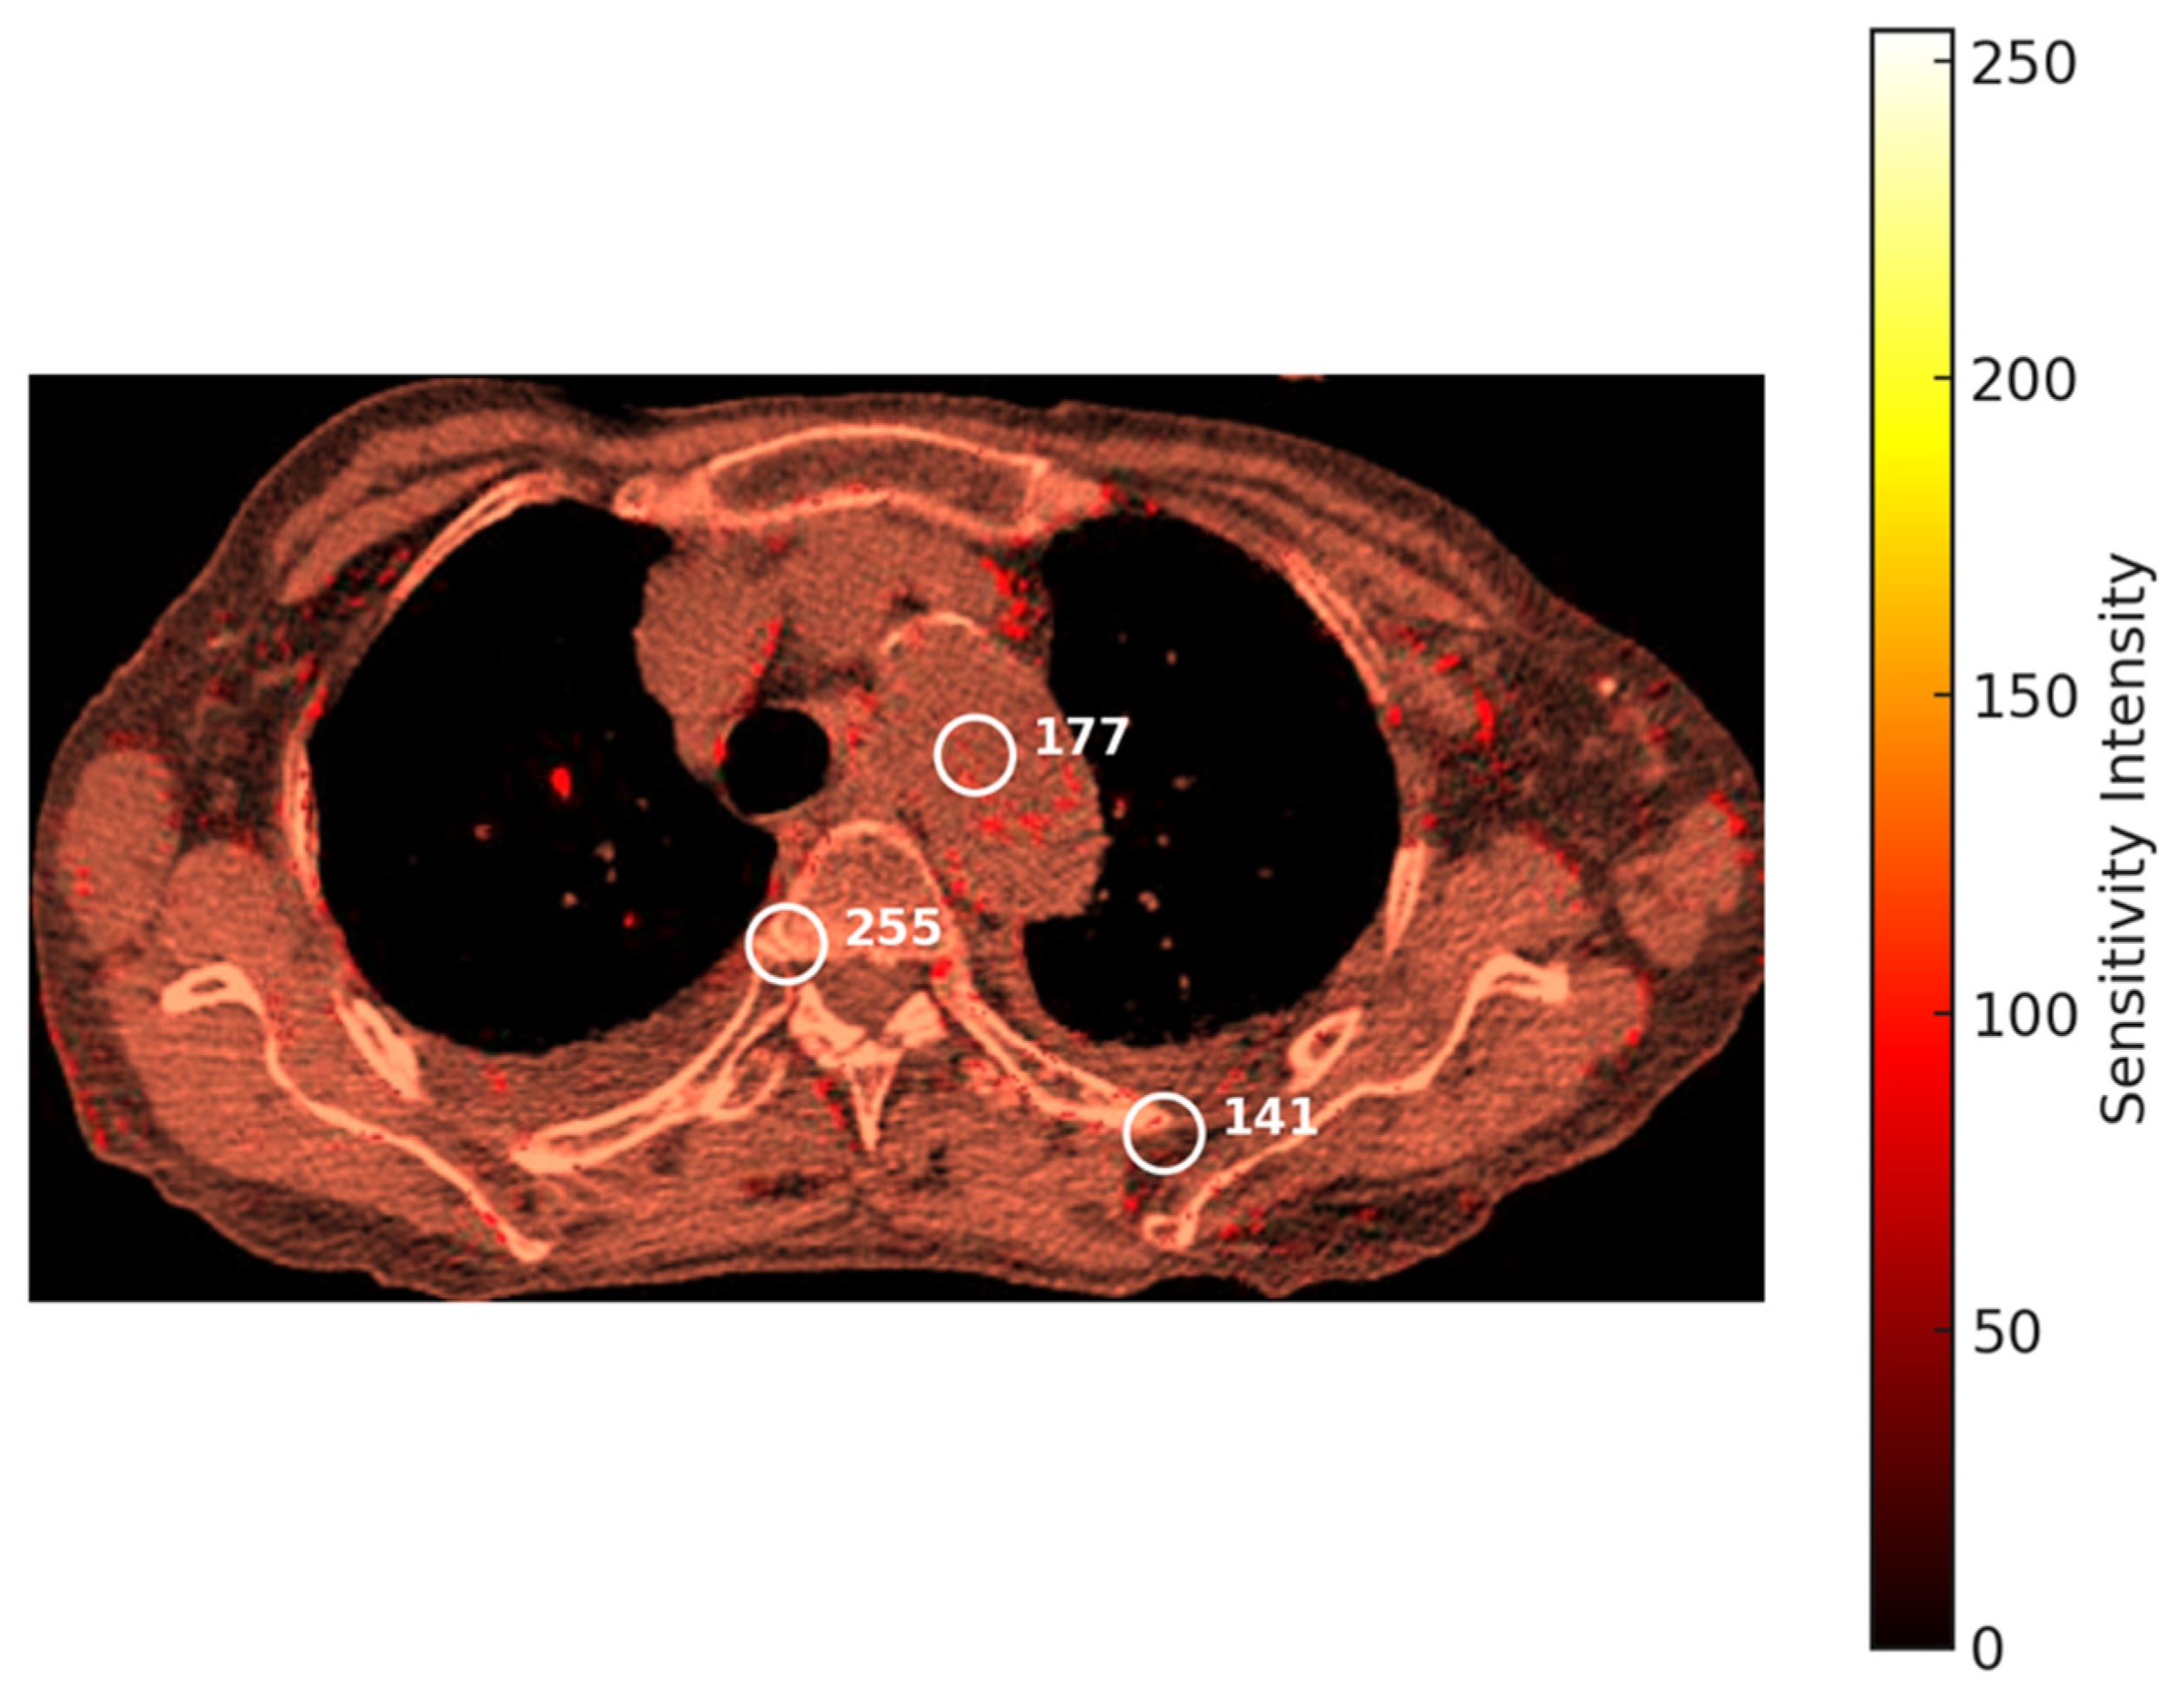

Figure 6 shows the heatmap output of PLI, which is a powerful means to visualize and interpret the complex relationship between the data points and fuzzy sets; numerical annotations depict specific sensitivity intensity values (e.g., 255, 177, 141) at key regions of interest, emphasizing the model’s focus on potentially critical areas in the image. This visualization allows a detailed understanding of the patterns and correlations relevant to the identification of potential malignancy [47]. By representing the fuzzy membership values as heatmaps, with lighter colors indicative of higher membership values—and hence a higher weight and likelihood of malignancy—darker colors signifying lower values, which means minimal risk, and the model generates an intuitive yet informative visual output. This allows for improved interpretability of the classification decisions where complex and ambiguous relations can be depicted in a clear and accessible format. While the heatmaps present the results of classification, they also serve to depict hidden patterns and associations from the data that would have otherwise been hidden. By mapping intensity and the distribution of fuzzy membership values across anatomical regions, this model allows for in-depth spatial correlations and subtle indicators of malignancy. This is further enriched with the weighted contribution from various anatomical segments within the heatmap, hence giving detailed insight into the areas of concern for higher risk or anomalies. This layered, data-driven visualization not only strengthens diagnostic accuracy but also supports clinicians in prioritizing areas for closer examination and enhancing the overall risk assessment [45].